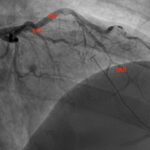

This case report discusses a 36-year-old male who presented to the emergency department with an atypical story for acute coronary syndrome (ACS). Initially, the patient was felt to have a non-diagnostic electrocardiogram (ECG). Once the laboratory test results were obtained and the initial high-sensitivity troponin was noted to be elevated, the initial ECG was again reviewed. The patient was felt this time to have an abnormal ECG, demonstrating borderline ST elevation in leads I, aVL, and V2-V5. The interventional cardiologist on call was contacted, and the cardiac catheterization lab was activated. Upon left heart catheterization, the patient was found to have a spontaneous coronary artery dissection (SCAD) of the distal left anterior descending (LAD) artery. Post-catheterization, the patient was observed on cardiac telemetry and started on dual antiplatelet therapy. Echocardiogram revealed a preserved ejection fraction (EF), but hypokinesis of the apical anterior, anterolateral, inferior, and apical myocardium. The patient was discharged within 48 hours without any complications.